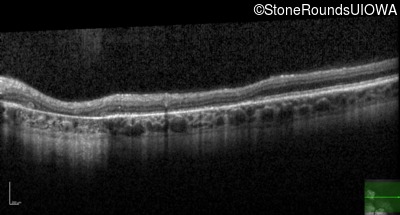

Optical Coherence Tomography - Left - 20/30 +1 sc

Exemplar / OCT Stack